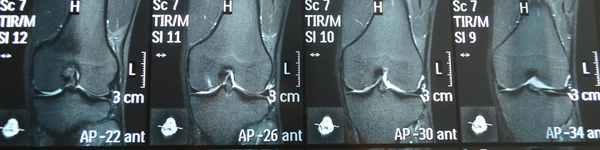

先说下我的诊断结果:右膝(5.6号MRI):内、外侧半月板后角损伤一到二度 关节及髌上囊积液 左膝(好像是4.29号拍的):股骨髁骨挫伤 关节及髌上囊积液。

在六月底考察课结束,考试课办了缓考,我爸把我接回家。一回家就跟父母讲了这个药,他们因为我的腿很担忧和发愁,就说买一盒试试吧。我在官网找了笑笑姐聊,觉得她很耐心贴心,态度很好很专业的感觉,让我加深了对这个品牌的信任,劝说了妈妈用银行汇款买了三盒。我从七月初开始吃到现在。我在将近吃了一盒以后,发现关节弹响好了,这让我信心大增,想着再吃3个月应该就好了。(结果比我的预期还好)前几天去做核磁,检查结果是:膝关节少量积液。我看到这个结果简直要高兴的蹦起来,但我的腿让我只能站着。。。虽然核磁显示好了,但我现在走路多了依然关节会疼,医生也告诫我还不能运动或深蹲,否则容易复发。但这个结果已经让我很满意了,我才吃了一个多月呀,真是个奇迹呢,软骨粉功不可没!(谢谢你咯)